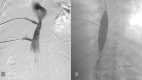

Figure 10

Figure 10. Cavogram showing tight stenosis in the hepatic IVC segment with venous collaterals and focal occlusions in the hepatic vein

IVC: Inferior vena cava

Figure 11

Figure 11. IVC stenosis balloon angioplasty and hepatic vein stenting